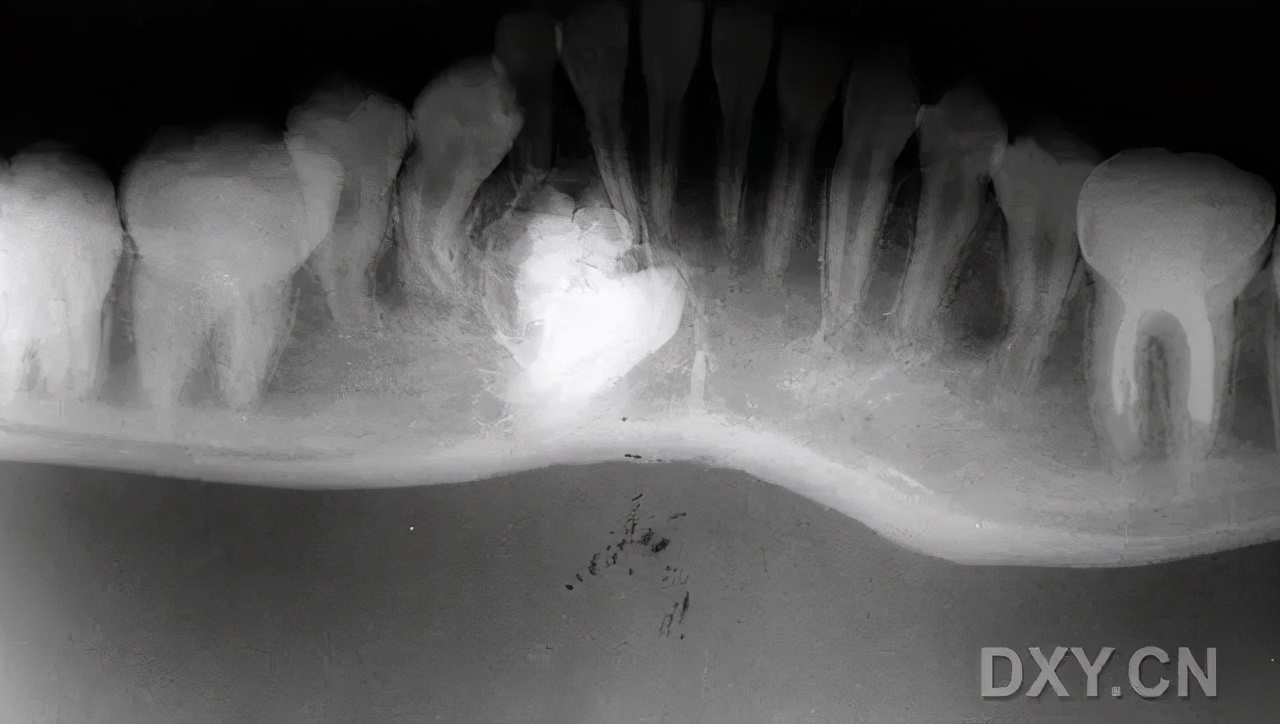

牙源性囊肿可以分为含牙囊肿,也就是老刘那种,一般在中青年之间产生的比较多,所含牙为未萌出的恒牙或额外牙。停留在牙槽骨中的未萌出恒牙可刺激造釉细胞,使呈增殖性变并产生分泌物而形成囊肿。牙釉质被包围在囊内,囊肿包膜为纤维组织构成,内膜为鳞状上皮。囊腔内含黄色或棕色液体;还有牙根囊肿,通常好发于老年人,为牙根感染,牙髓坏死,由牙根尖肉芽肿退行性变形成,他们都需要摘除囊肿然后处理病牙。比如老刘掉的半口牙,还得是让牙医给他再种上。